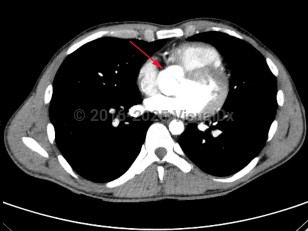

Congenitally abnormal aortic valve with only two functional valve cusps, usually due to fusion of two of the cusps. This is associated with valvular stenosis and/or insufficiency, as well as abnormalities of the aorta including aneurysms and coarctation. It may occur alone or with other cardiovascular abnormalities such as ventricular septal defect, patent ductus arteriosus, and sinus of Valsalva aneurysm.